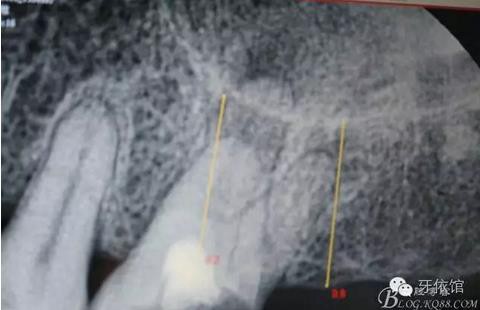

患者女,45歲,右上6于多年前牙髓失活后充填,未作冠,術(shù)前不久,進食時不幸劈裂。檢查發(fā)現(xiàn):右上6充填物脫落,近遠中向縱劈,x光見根管內(nèi)無充填物。同時有右上7、右下7缺失。計劃:右上6,7,右下7種植修復(fù)。右上6為即可種植,同時做內(nèi)提。

X光片